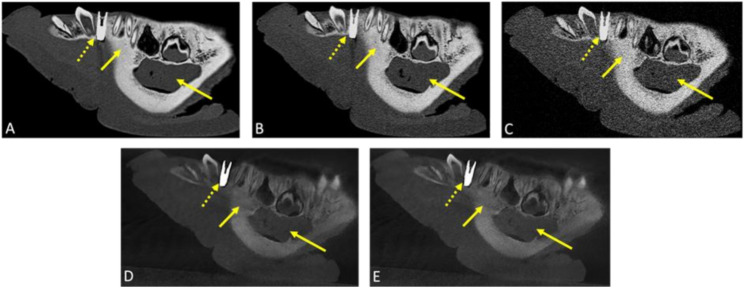

Methods: This ex vivo comparative study of porcine specimens assessed five imaging protocols with both CBCT and PCD-CT at three effective radiation dose levels (high: 360µSv, standard: 145µSv, low: 20µSv) to evaluate image quality, artifact burden, metal artifact susceptibility, and quantitative bone measurements in the mandibular region. Three blinded readers analyzed the data using a 5-point Likert scale (5 = highest to 1 = lowest rating) and performed linear bone measurements at implant planning sites. Statistical analysis included descriptive statistics and inter-reader reliability assessment using intraclass correlation coefficients (ICC).

Results: Each reader evaluated 30 data sets (12 CBCT, 18 PCD-CT), with 24 implant planning sites per imaging protocol. High-dose PCD-CT demonstrated the best image quality and diagnostic interpretability (4.89 ± 0.27), followed by standard-dose PCD-CT and CBCT (4.50 ± 0.73; 4.33 ± 0.61), with low-dose protocols showing intermediate quality with higher artifact burden. In comparison to CBCT, PCD-CT demonstrated superior performance in reducing implant-induced artifacts across all protocols. Quantitative bone measurements showed minimal variability, meeting clinical precision requirements for computer-assisted implant surgery. Both qualitative (ICCs:0.70-0.89; p < 0.001) and quantitative (ICCs:0.79-1; p < 0.001) analyses demonstrated high reliability, regardless of the reader's experience.